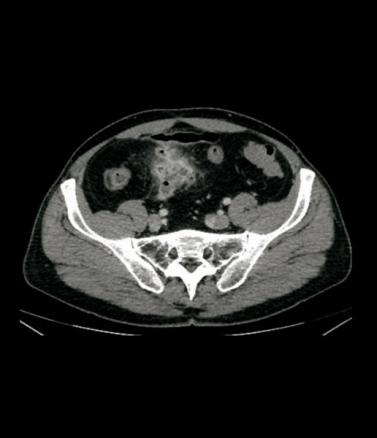

Aspect de collection hydro-aérique au contact de l’iléon correspondant à un abcès, avec hyperhémie du méso (signe du peigne).